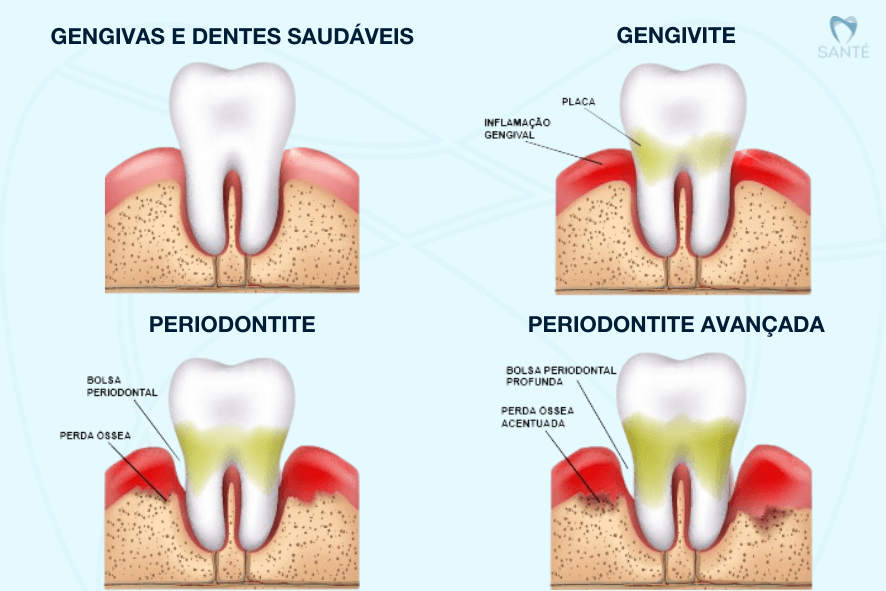

Principais condições da Doença Periodontal:

- Gengivite: inflamação superficial da gengiva, com sangramento e vermelhidão.

- Periodontite: estágio avançado da gengivite, que compromete o osso e pode levar à perda dentária.

Não é normal a gengiva sangrar durante a escovação ou uso do fio dental. O sangramento gengival geralmente indica gengivite, causada pelo acúmulo de placa bacteriana e tártaro. Se não for tratada, a gengivite pode evoluir para periodontite, causando perda óssea ao redor dos dentes.

- Gengivite: inflamação mais superficial, com gengiva vermelha, inchada, que sangra facilmente.

- Periodontite: estágio mais avançado, atinge osso e ligamento, pode causar retração gengival, mau hálito, pus e dentes moles.

A principal causa de perda óssea ao redor dos dentes é a periodontite, inflamação que destrói os tecidos de suporte. Outras causas incluem perda dentária sem reposição, traumas, uso inadequado de próteses e até fatores sistêmicos, como osteoporose.

Sim, a gengivite tem cura quando tratada com profilaxia (limpeza profissional) e boa higiene oral. Porém, se não for tratada, pode evoluir para periodontite. O osso perdido com a evolução da periodontite geralmente não se regenera, ele deixa de ser exatamente como antes. Essa condição de perda óssea deve ser estabilizada e acompanhada com o tratamento periodontal. As limpezas periódicas adiam e evitam a extração do dente.